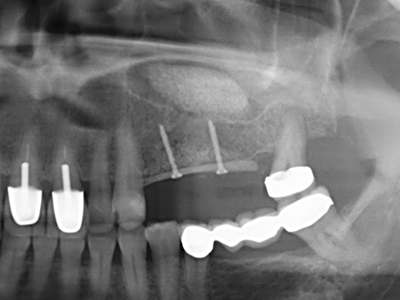

Bei der Knochenblockentnahme zeigen sich weitere Vorteile für die Piezochirurgie: Neben der bereits beschriebenen hohen Präzision bei der Osteotomie stellt sich gerade die Verwendung der dünnen Sägespitzen als besonders materialschonend heraus. Bei der Verwendung insbesondere von Lindemannfräsen sind mit deutlich höheren Entnahmeverlusten durch die dickere Instrumentenspitze zu rechnen (Lakshmiganthan, Gokulanathan et al. 2012). Die insbesondere bei retromolar entnommenen Blocktransplantaten notwendige basale Abtrennung wird durch speziell hierfür vorgesehene rechtwinklige Sägen erleichtert, so dass die Piezochirurgie als präzises, übersichtliches und sicheres Verfahren zur retromolaren Knochenblockgewinnung angesehen wird (Happe 2007) (Abb. 1-12).

Sollen chirurgische Eingriffe mit unmittelbarer Knochenbeziehung an empfindlichen Strukturen wie Blutgefäßen oder Nerven erfolgen, so bergen rotierende Instrumente ein erhebliches Potential an iatrogener Schädigung. Gerade bei Nervdarstellungen nach iatrogener Schädigung, oder aber im Zuge einer Nervlateralisation für resektive und rekonstruktive Eingriffe oder Implantatinsertionen können piezoelektronische Geräte hilfreich sein Knochendeckel zu präparieren und nervnahe Hartgewebsanteile zu entfernen (Abb. 17-20). Ein leichter Kontakt des Nervstrangs zur Piezospitze bleibt dabei in der Regel folgenlos – allerdings kann eine unvorsichtige Vorgehensweise mit sägeartigen Bewegungen bzw. Ansätzen bei noch vorhandener knöcherner Unterlage durchaus temporäre oder aber auch permanente Nervschädigungen verursachen. Das Risiko einer solchen Schädigung wird jedoch als wesentliche geringer eingeschätzt als unter Anwendung von Säge- oder Fräsinstrumenten (Pereira, Gealh et al. 2014).

Wie sich in der Vergangenheit gezeigt hat stellt prinzipiell jeder knochenchirurgische Eingriff eine mögliche Indikation für die Piezochirurgie dar. So lässt sich die Präparation des mobilen Segmentes bei der Distraktionsosteogenese (Abb. 23-25) und der Sandwichosteotomie mit speziellen Ansätzen bewerkstelligen, ohne die für den Erfolg beider Techniken essenzielle Blutversorgung des krestalen Anteils zu gefährden (Gonzalez-Garcia, Diniz-Freitas et al. 2008).

Für die Entnahme von Implantaten ist die Präparation eines vestibulären Knochendeckels möglich, der nach Entfernung der Implantatschraube refixiert wird und auf diesem Wege die Kontur des Alveolarfortsatzes erhält.

Weitere Einsatzgebiete ergeben sich in der Kieferhöhlenchirurgie: Hier können nach konzentrischer Präparation eines in der Regel trapezförmigen Knochendeckels der fazialen Kieferhöhlenwand Pathologien und Fremdkörper aus der Kieferhöhle entfernt werden. Der Knochendeckel wird nach Abschluss des intra-antralen Operationsanteils reponiert und durch Verkeilen oder adaptierende Nähte gegen Dislokation gesichert.